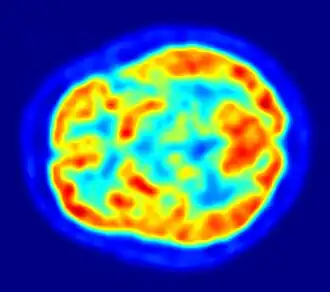

Компьютерное представление изображения поперечного сечения головного мозга человека в искусственных цветах на основе сцинтилографии в позитронно-эмиссионной томографии